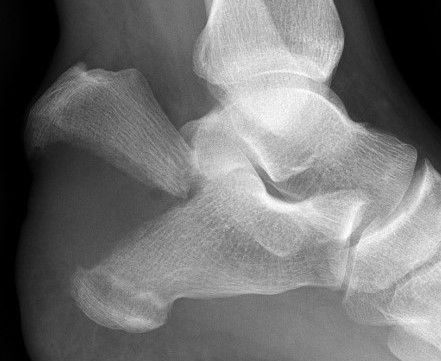

Imaging

Achilles tendon performs a deforming force

Posterior skin can be threatened and become ischemic / necrotic